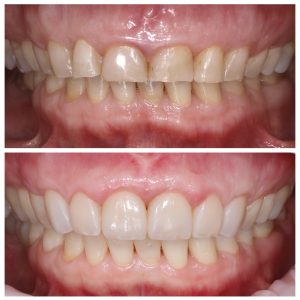

Estetinis plombavimas ant pacientės priekinių dantų

Galutinis rezultatas – natūrali ir autentiška šypsena. Tačiau svarbi ne tik atkurta dantų estetika. Mūsų odontologai pabrėžia, jog po gydymo, kai atliekamas visų dantų plombavimas ir atkūrimas, stipriai pagerėja sąkandžio būklė. Atkurta pilnavertė dantų anatomija apsaugo žandikaulio sąnarius nuo pertempimo ar priešlaikinio susidėvėjimo.

Visų dantų plombavimas prieš ir po Nudilusių dantų estetinis plombavimas prieš ir poVisų nudilusių dantų plombavimas prieš ir poViršutinis dantų lankas prieš ir po plombavimoApatinis dantų lankas prieš ir po plombavimo